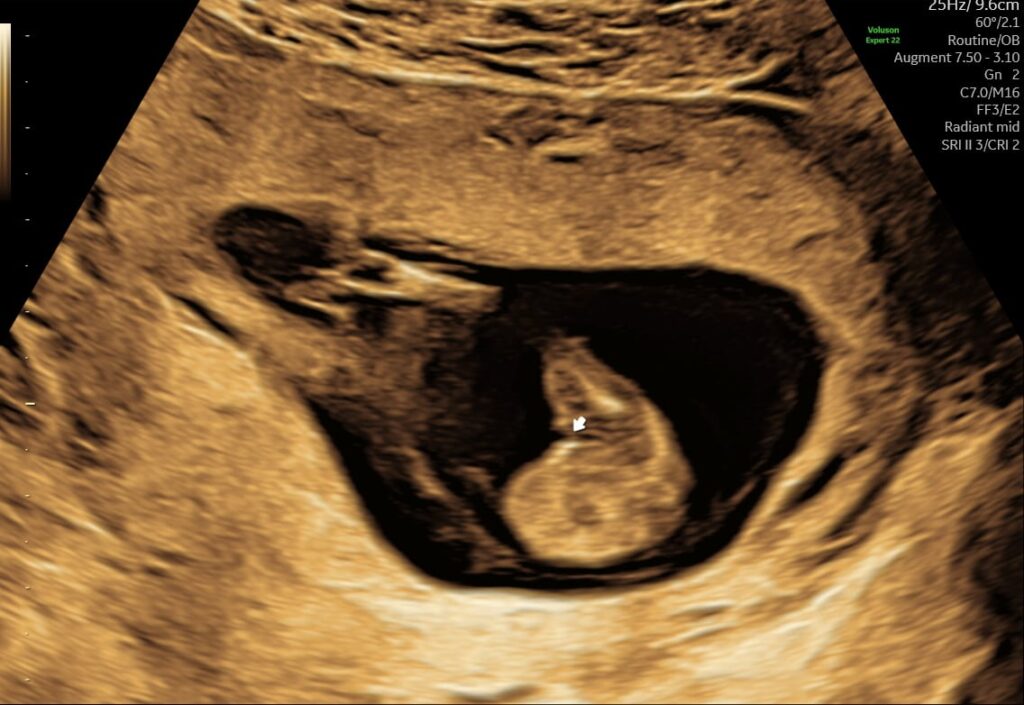

Du kan blive scannet så tidligt som uge 5+0. Dog kan vi først sikre at der kan ses hjerteblink fra uge 6+3. Se her for at beregne så præcis en termin som muligt ud fra hvad du ved om din graviditet.

Hvis du vælger en super tidlig scanning så læs her om hvad man kan se hvornår.

Hvornår kan jeg blive scannet fra maven?

Det er individuelt hvornår man kan se graviditeten klart på en abdominal scanning. Vægt og livmoderens placering betyder meget. Vi anbefaler vaginale scanninger frem til uge 10+0 for at få de bedste billeder.

Det sker ca. i uge 9 hvor fostrets kønsorganer er ved at blive dannet. Det er dog alt for tidligt i uge 9 at kunne se det via en kønsscanning.